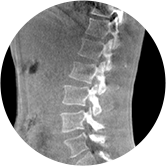

颈椎

腰椎

VR体绘制重建